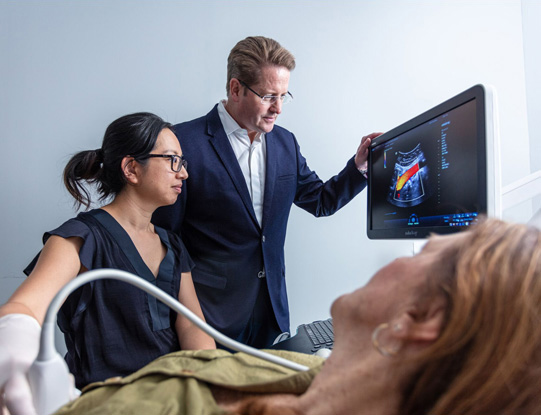

Dr Anthony Freeman is a specialist vascular and endovascular surgeon working together with Sydney Vascular Ultrasound to provide a full-service model of care for the comprehensive diagnosis, treatment and post-operative care of patients with venous and arterial disorders.

Dr Freeman and Sydney Vascular Ultrasound provide comprehensive diagnosis, treatment and expert care in the management of all vascular conditions.

Vascular Ultrasound

Specialist vascular ultrasound diagnostic services are an integral part of our care model.